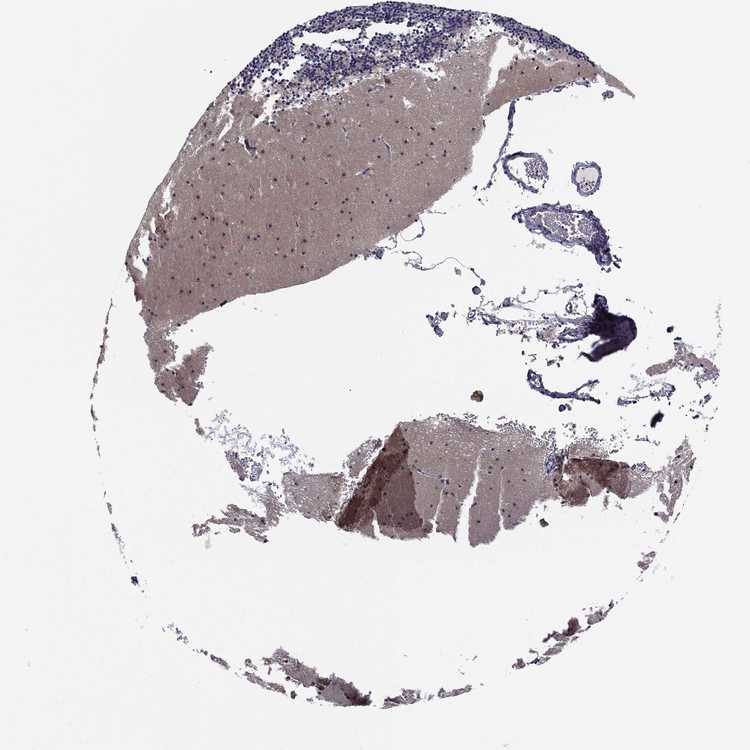

BRAIN CEREBELLUM Show tissue menu

CEREBELLUM - Expression summary

CEREBELLUM - Antibody stainingi

Antibody staining in the annotated cell types in the current human tissue is reported as not detected, low, medium, or high, based on conventional immunohistochemistry profiling in selected tissues. This score is based on the combination of the staining intensity and fraction of stained cells.

Each image is clickable and will lead to virtual microscopy that enables deeper exploration of all samples and also displays staining intensity scores, fraction scores and subcellular localization as well as patient and tissue information for each sample.

Antibody HPA065983Antibody HPA071879

Purkinje cells HighLow

Cells in granular layer MediumNot detected

Cells in molecular layer HighNot detected